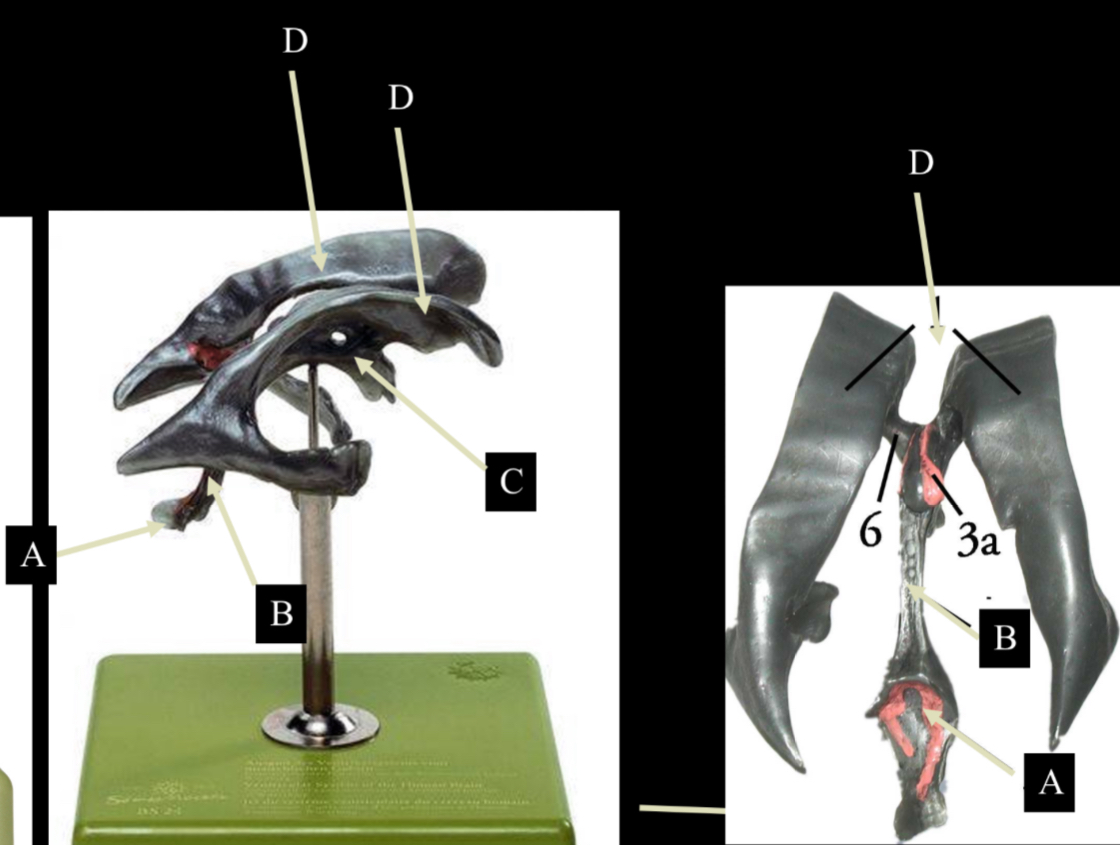

What is D?

lateral ventricle

Imagine thin membrane separating the 2 lateral ventricles

septum pellucidum

What is C?

3rd ventricle

What is B?

cerebral aqueduct

What is A?

4th ventricle

What is below A at the very end?

central canal (spinal cord)